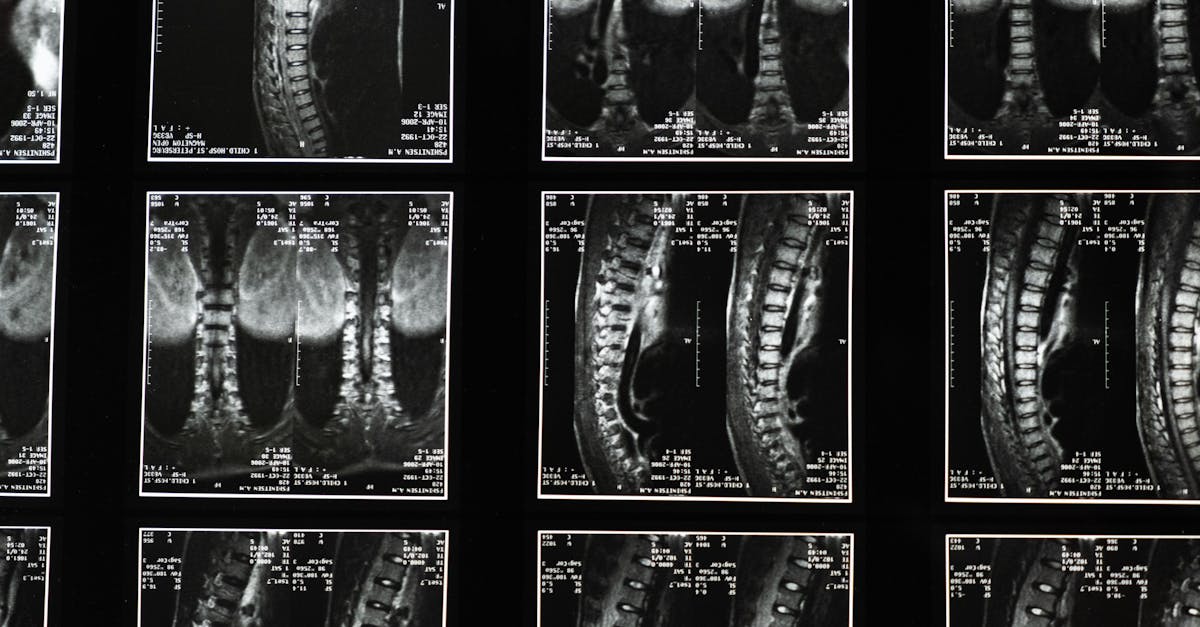

«`html ¿Sufre de ciática? Deje que Pulse Align le inspire a encontrar alivio.¿Siente un dolor debilitante debido a la ciática? Esta afección puede afectar gravemente su vida diaria, dificultando tareas sencillas como agacharse o realizar sus actividades favoritas. En Pulse Align, ofrecemos un enfoque holístico y compasivo que enfatiza la salud neuromuscular, la mejora de la postura y la recalibración holística para aliviar las molestias y promover el bienestar general. Este artículo le guiará a través de estrategias efectivas para aliviar sus problemas de ciática y recuperar su vitalidad. Entendiendo la ciáticaLa ciática se refiere al dolor que se irradia a lo largo del trayecto del nervio ciático, que se extiende desde la zona lumbar, a través de los glúteos y por cada pierna. Muchas personas sufren afecciones asociadas, como hernias discales, dolor lumbar y estenosis espinal, que provocan una gran variedad de molestias, incluyendo dificultad para agacharse o permanecer sentado durante períodos prolongados. Ejercicios de fortalecimiento del core para el alivioRealizar ejercicios de fortalecimiento del core es crucial para las personas que sufren de dolor lumbar. Un ejercicio efectivo es la inclinación pélvica. , que puede ayudar a estabilizar y fortalecer la región lumbar. Al incorporar este movimiento a su rutina, no solo proporciona soporte a la zona lumbar, sino que también alivia la presión sobre el nervio ciático. Además, incluir ejercicios de tronco puede mejorar la estabilidad y la coordinación general.Importancia de la corrección postural Mejorar la postura es otro aspecto vital para controlar la ciática. Usar una silla ergonómica al trabajar puede reducir significativamente la tensión en la espalda. Revise regularmente su postura al dormir para detectar dolor de espalda; dormir de lado con una almohada entre las rodillas promueve la alineación de la columna vertebral y previene las molestias. Una buena postura ayuda a mantener la simetría corporal, asegurando una recalibración óptima del sistema nervioso.Estiramientos efectivos para el dolor lumbar Incorporar estiramientos para el dolor lumbar a su rutina puede mejorar la flexibilidad y reducir la tensión muscular. Concéntrese en estiramientos dirigidos al músculo piriforme, ya que la rigidez en esta zona puede agravar el síndrome piriforme. Estos estiramientos no solo ayudan a aliviar el dolor de ciática, sino que también contribuyen al bienestar general al estimular el flujo de energía a través del cuerpo.Control de Peso y Dolor de Espalda El control de peso es fundamental para aliviar el dolor de espalda. Mantener un peso corporal saludable disminuye la tensión en la columna lumbar, lo que facilita la recuperación. Al combinar una dieta equilibrada con técnicas adecuadas de levantamiento de pesas, puedes sentar las bases para un bienestar a largo plazo.Llamada a la acción: Descubre tu camino hacia el bienestar ¿Listo para actuar? En Pulse Align, nos enorgullecemos de ofrecer planes de ejercicio personalizados adaptados a tus necesidades específicas. Descubre soluciones holísticas, incluyendo los beneficios de la terapia de ondas de choque para el dolor lumbar, y descubre cómo podemos ayudarte en tu proceso de recuperación. Reserva tu consulta hoy mismo en una de nuestras clínicas cercanas en Montreal, La Prairie o Ciudad de Panamá, y emprende el camino hacia una vitalidad renovada y el alivio de la ciática.Aspect Enfoque Pulse AlignBienestar Holístico Nos centramos en el bienestar integral, no solo en el alivio de los síntomas.Fortalecimiento del Core Hace hincapié en ejercicios específicos que mejoran la estabilidad muscular para un mejor soporte.Corrección Postural

TAGMED ofrece una solución innovadora y no quirúrgica, diseñada específicamente para tratar problemas discales de moderados a graves, como hernias discales, protrusiones discales y estenosis espinal. Al reducir suavemente la presión sobre los discos y nervios afectados, esta técnica especializada ayuda a mejorar la movilidad, aliviar el dolor y favorecer el proceso natural de curación del cuerpo. Si se ha estancado con otras terapias, descubra cómo el enfoque de descompresión basado en la evidencia de TAGMED puede ayudarle a retomar una vida activa y cómoda. ¿Ha probado tratamientos convencionales y aún sufre de dolor de espalda persistente debido a una afección discal grave? El mecanismo de acción consiste en la descompresión neurovertebral de TAGMED, que aplica una fuerza de tracción controlada y progresiva a la columna vertebral. Este método aumenta eficazmente el espacio entre las vértebras, reduciendo la presión sobre los discos intervertebrales y las raíces nerviosas. Como resultado, promueve una mejor circulación de líquidos en la zona afectada. Esta circulación mejorada ayuda a reducir la inflamación y aliviar el dolor, ofreciendo una solución fiable y no invasiva para personas con dolor de espalda crónico. Beneficios específicosEste enfoque no invasivo alivia eficazmente el dolor crónico y los síntomas asociados con afecciones como hernias discales o estenosis espinal. Al reducir la presión sobre las estructuras nerviosas y optimizar la circulación de líquidos alrededor de los discos, los pacientes pueden experimentar una recuperación más rápida y una mejor calidad de vida. Esto convierte a la terapia de TAGMED en una opción atractiva para quienes buscan alternativas a los tratamientos tradicionales. Comparación con otros tratamientosEn comparación con otros tratamientos comunes, como analgésicos, inyecciones de corticosteroides o cirugía, la tecnología de descompresión neurovertebral de TAGMED destaca. No requiere intervenciones invasivas y minimiza los riesgos relacionados con la medicación. Muchos pacientes encuentran una recuperación potencialmente más rápida, lo que hace que este enfoque sea atractivo para quienes buscan alternativas más seguras y basadas en la evidencia para el manejo de afecciones como la enfermedad degenerativa del disco o la hernia discal. Casos prácticos o testimoniosEjemplos reales resaltan el éxito de la terapia de TAGMED. Los pacientes han reportado un alivio duradero del dolor y una reanudación más rápida de sus actividades diarias. Un testimonio describió cómo el enfoque de TAGMED redujo su dependencia de fármacos, permitiéndoles retomar un estilo de vida más activo. Estos testimonios de primera mano ilustran los resultados tangibles de esta técnica terapéutica, reforzando sus ventajas prácticas para los pacientes que sufren de dolor crónico. Nuestra misión En Pulse Align, nuestra misión es brindar tratamientos basados en la evidencia y centrados en el paciente que aborden las causas subyacentes del dolor y la disfunción. Al integrar técnicas y tecnologías avanzadas, nos esforzamos por empoderar a cada persona para que tome el control de su salud, garantizando una atención de alta calidad, un alivio duradero y una mejor calidad de vida.

Desbloqueando el alivio: Terapia de descompresión espinal avanzada de TAGMED TAGMED ofrece una solución innovadora y no quirúrgica diseñada específicamente para tratar problemas discales de moderados a graves, incluyendo afecciones como hernias discales, protrusiones discales y estenosis espinal. Al reducir suavemente la presión sobre los discos y nervios afectados, esta técnica especializada mejora la movilidad, alivia el dolor y apoya el proceso natural de curación del cuerpo. Si se ha estancado con otras terapias, descubra cómo el enfoque de descompresión basado en la evidencia de TAGMED puede ayudarle a retomar una vida activa y cómoda. ¿Ha probado tratamientos convencionales y aún sufre de dolor de espalda persistente debido a una afección discal grave?Mecanismo de acción La terapia de descompresión neurovertebral de TAGMED aplica una fuerza de tracción controlada y progresiva a la columna vertebral. Este método aumenta eficazmente el espacio entre las vértebras, reduciendo la presión sobre los discos intervertebrales y las raíces nerviosas. Al promover una mejor circulación de líquidos en la zona afectada, esta técnica no solo ayuda a reducir la inflamación, sino que también alivia el dolor, ofreciendo una solución fiable y no invasiva para personas con problemas crónicos de espalda. El proceso estimula los mecanismos naturales de curación del cuerpo a la vez que alivia los síntomas asociados con afecciones como la ciática y la enfermedad degenerativa del disco. Beneficios específicos Este enfoque no invasivo puede aliviar eficazmente el dolor crónico y los síntomas asociados a afecciones como hernias discales o estenosis espinal. Al reducir la presión sobre las estructuras nerviosas y optimizar la circulación de líquidos alrededor de los discos, la terapia de TAGMED puede acelerar la recuperación y mejorar la calidad de vida de muchos pacientes que buscan alivio del malestar persistente. Ya sea que padezca protuberancias discales, síndrome facetario o incluso braquialgia, los pacientes a menudo experimentan mejoras sustanciales tanto en la movilidad como en los niveles de dolor.